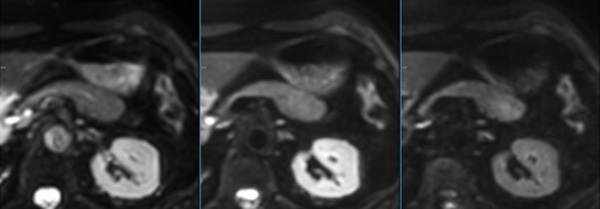

Pancreas imaging with dS Zoom